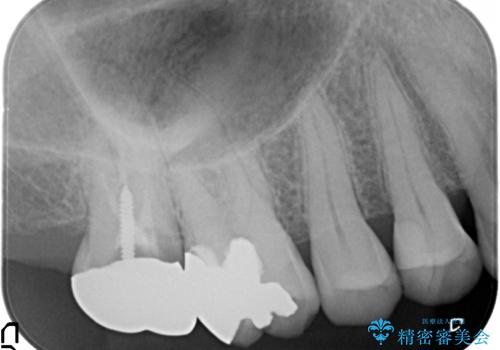

歯髄方向 歯肉方向へと深い 2種類の大きな虫歯

#17は失活歯で歯肉方向への縁下カリエス、#16は生活歯であるものの歯髄ギリギリの処置となるであろうとが予想される治療です。

歯周外科、マイクロスコープを用いた虫歯治療を行い歯を残す治療計画を立てます。